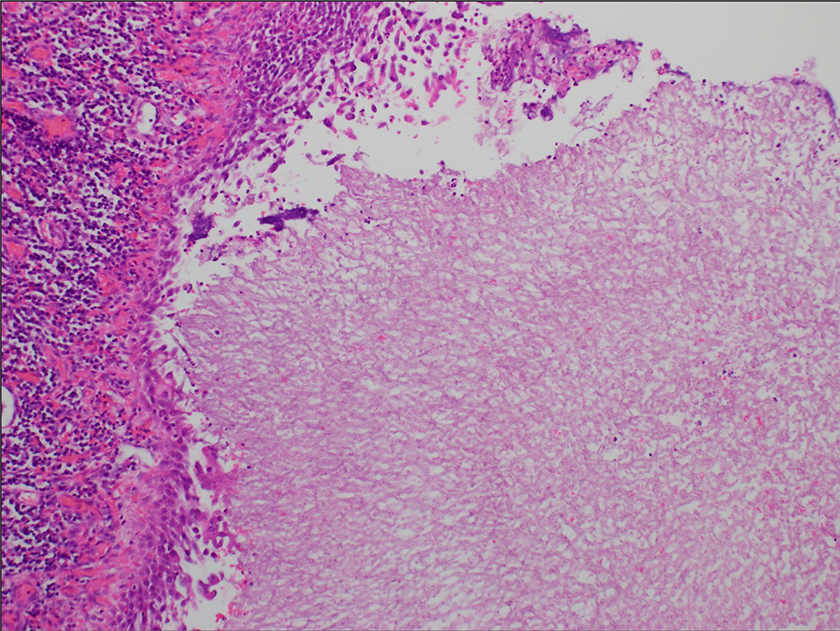

H&E stain of lung airspace, ×20. The fungal organisms are on the right side and the cystic wall with inflammatory cells is on the left. There is extensive necrosis and cavitation of the lung, with aggregates of septate fungal hyphae present within the cavitated space as well as within the larger airways. No angioinvasion is identified.

Describe the Histologic Features Seen in Figures 2 and 3

Figure 2 shows extensive necrosis and cavitation of the lung with aggregates of septate fungal hyphae present within the cavitated space as well as within the larger airways. The fungal organisms are on the right side and the cystic wall with inflammatory cells is on the left. No angioinvasion is identified. Figure 3 shows higher magnification from the necrotic center of the fungus ball (aspergilloma) showing numerous slender and septate hyphae that branch at acute angles.